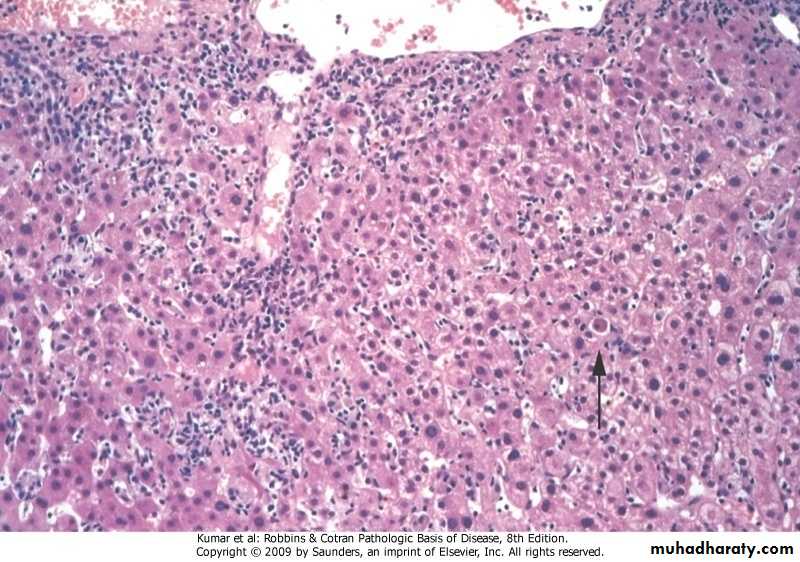

Acute viral hepatitis

Ballooning degeneration